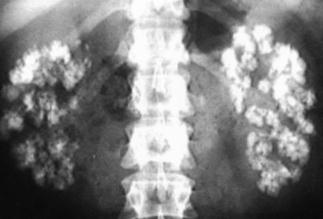

Distal RTA occurs with a number of conditions, amongst them

classically Sjogrens syndrome but also other autoimmune conditions. Cisplatin

has been mentioned as one of the causes of idRTA in this blog earlier. idRTA is a common cause of nephrocalcinosis – with or without

stones – and it has a number of prominent victims as also mentioned in a

previous post.